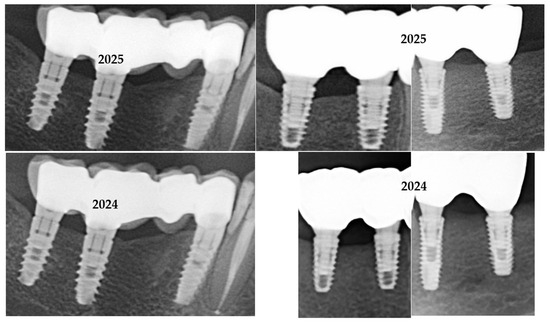

In Figure 1 are presented two cases, one cemented with Fuji Plus and one with DentoTemp™.

Figure 1.

Sections of orthopantomographs (OPGs) showing two cemented partial restorations monitored between 2020 and 2025. The left panels depict a metal–ceramic three-unit prosthesis cemented with DentoTemp™, while the right panels show a zirconia three-unit prosthesis cemented with Fuji Plus®. Images are arranged chronologically from baseline (2020) to the most recent control (2025), illustrating stable peri-implant bone levels in both groups.